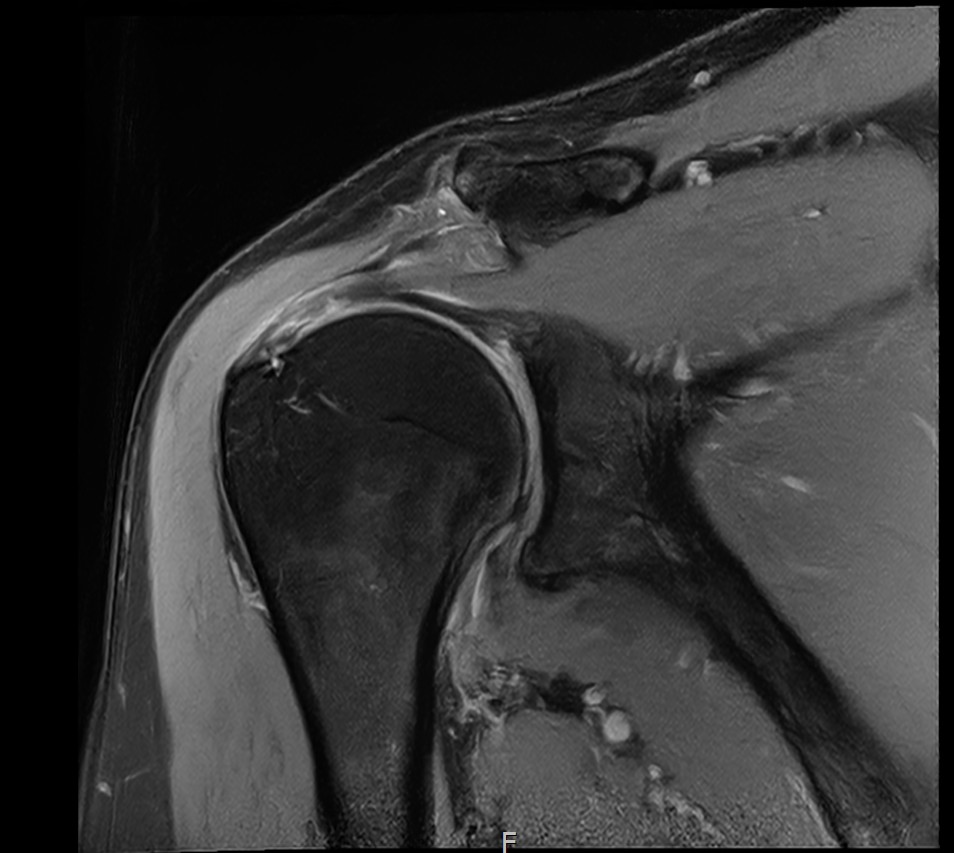

MRI와 초음파 검사 결과:

진단 결과:

- ✓관절면측 부분파열: 약 50%

- ✓점액낭면측 부분파열: 약 35%, 인대 얇아짐 동반

- ✓25년간 반복 사용으로 인한 퇴행성 변화 동반

양쪽 모두 손상된 복합 파열이었습니다.